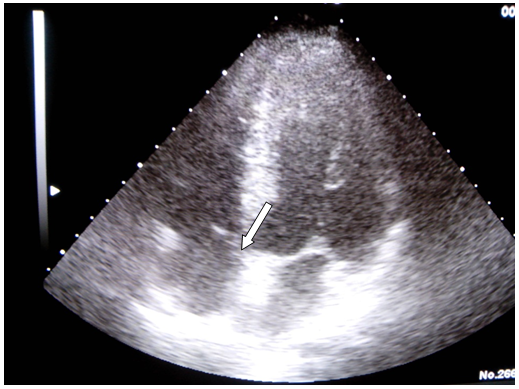

Furthermore, a chest CT scan was performed, showing a lung lesion in the low left lobe including left bronchus, lung lymphadenopathy, left pleura metastatis, left kidney stroke and bilateral suprarenal metastasis. A brain MRI confirmed right middle cerebral artery stroke, left posterior- inferior cerebellar artery stroke and right anterior cerebral artery stroke (Figure 3).

Figure 3Brain MRI, difussion-weighted images showing right middle cerebral artery stroke.